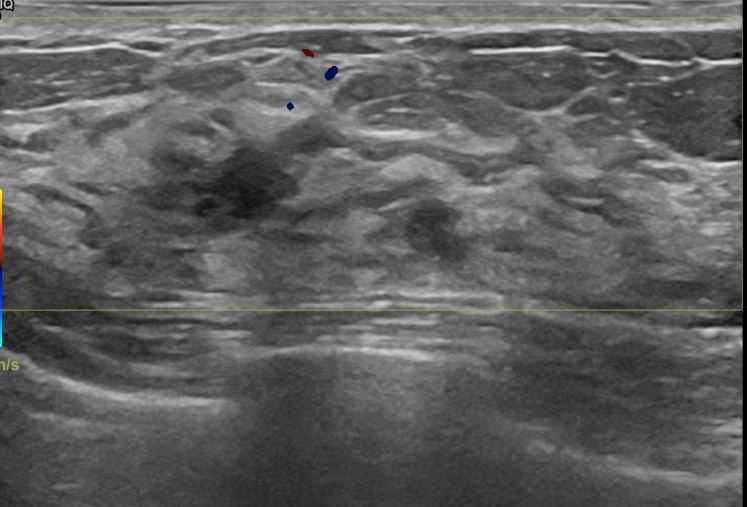

아산유외과개원후 669번째 유방암진단

상기환자 외부검사상 이상소견으로 내원하신 40대여성으로 우측에 의심스러운혹 조직검사시행해 유방암 진단되었습니다.